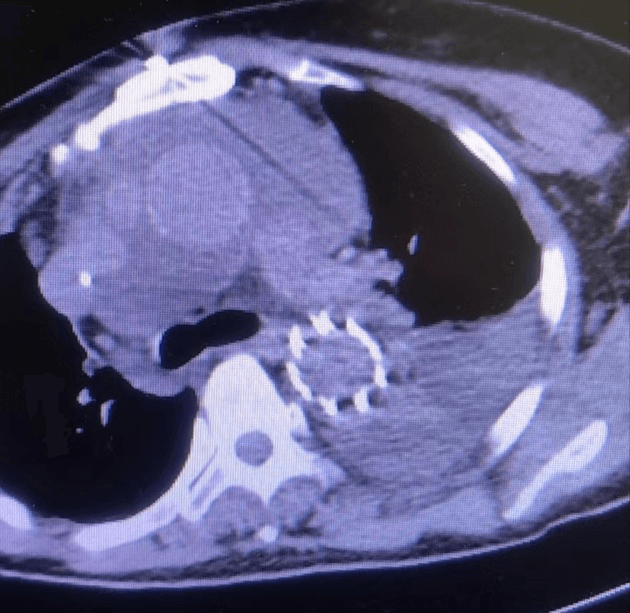

近日,我院急診科會診來了一位60歲女性患者,患者訴胸背部疼痛4小時余,疼痛劇烈,不能忍受,來院時血壓260/135mmHg,于當地縣醫院行大血管CTA檢查,提示主動脈夾層。新型冠狀病毒感染未完全康復的值班醫生一路小跑都氣喘吁吁前往急診科會診,一邊咳嗽一邊問診,由于患者病情危急,請示心外科武小剛科主任后分析:患者系主動脈夾層動脈瘤(A型),降主動脈近段可見明顯破口,升主動脈明顯增寬,根據超聲提示,目前考慮升主動脈已有新的破口,需急診行外科手術治療。與家屬溝通后積極降壓、止痛、備血等,進入夾層綠色通道,經過快速的術前準備,患者及早進入手術室,術中仔細剝離血管及周圍組織,小心翼翼的分離出受累血管,嚴格控制血壓,避免因血壓過高導致血管破裂,建立體外循環術中探查升主動脈可見1cm破口,驗證了術前的判斷;剪除掉破損血管,植入人工血管,仔細吻合每一根血管,既不能讓吻合口過小導致血液供應不足,也不能讓吻合口出血,一臺“升主動脈置換+全弓置換+象鼻術”需要經過長達6~8小時高精度操作,對醫生的耐力和精神都是一種考驗,經過6小時的手術,順利拆除“炸彈”。主刀醫師從手術室出來,已經是凌晨2點鐘,脫掉早已被汗水浸透的手術衣,癱軟的坐在椅子上,但患者轉危為安,再大的疲憊都是值得的。

術后復查恢復良好